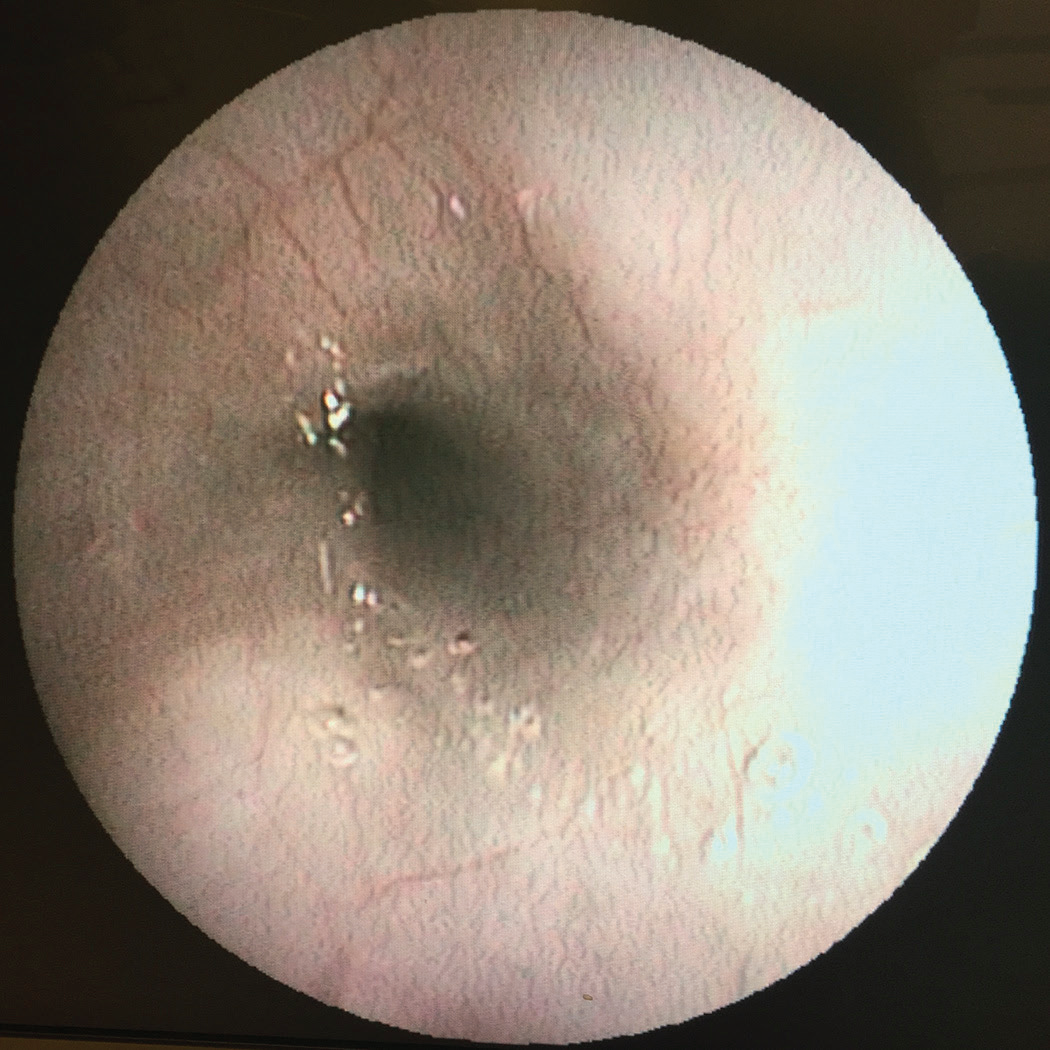

翻译:祁海丽;校对:石慧10 Figure 10.1 presents an endoscopic view of the greater curvature ...